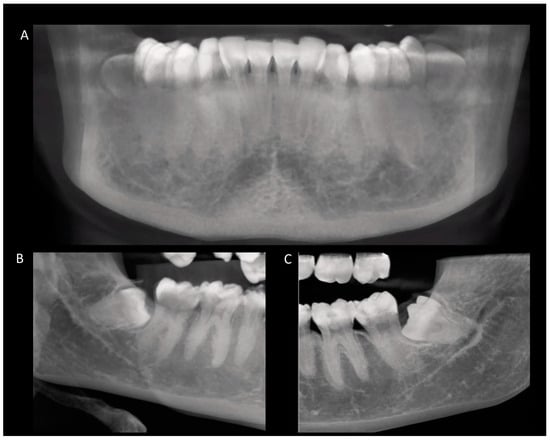

2. Materials and Methods

3.2. Positioning of Impacted Third Molars

3.3. Anatomical Relationship between the Root Apex of the Impacted Third Molar and the Mandibular Canal

3.4. Occurrence of External Root Resorption on the Distal Side of the Mandibular Second Molar